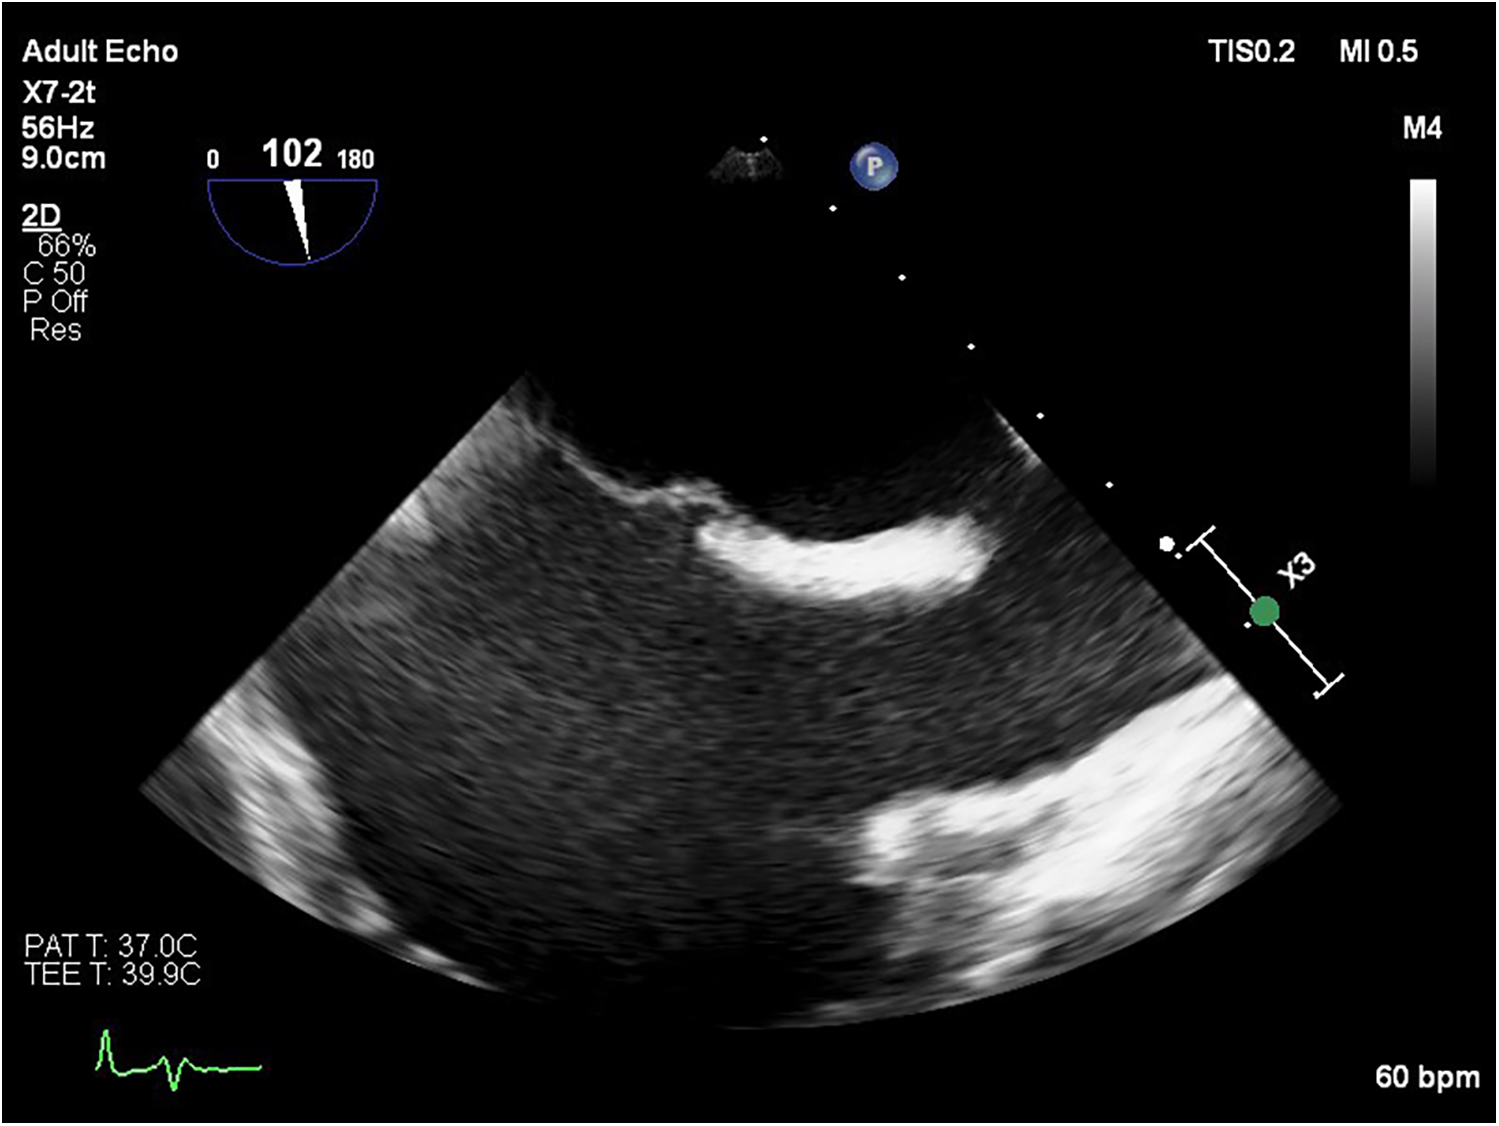

Transesophageal echocardiography (TEE) demonstrated a superior sinus venosus defect near the junction of the superior vena cava (SVC) and right atrium with left-to-right shunting. Two pacing leads pass through the defect from the SVC into the left side of the heart, with one lead affixed to the left atrium roof and the other extending through the mitral valve without any perforations into the left ventricle, where it is fixed to the interventricular septum. No intracardiac thrombi, or “smoke” and thrombi on pacemaker leads were observed during TEE (Figures 2, 3). A contrast-enhanced computer tomography (CT) scan of the chest was performed to further evaluate the suspected congenital defect and confirm the position of malpositioned pacing leads (Figure 4). CT imaging confirmed the presence of a superior sinus venosus defect located near the junction of the SVC and the right atrium. Moreover, CT revealed partial anomalous pulmonary venous return, with the right superior and middle pulmonary veins draining into the SVC. Given the patient's age, moderate frailty, and absence of significant clinical symptoms, a conservative approach was adopted. Lead extraction was not pursued due to high procedural risk. The patient was managed with lifelong oral anticoagulation with warfarin to mitigate the risk of systemic thromboembolism. Surgical correction of the anomalous pulmonary venous return was not indicated, as the patient remained hemodynamically stable without signs of volume overload. Ongoing follow-up includes regular assessment of anticoagulation status, pacemaker function, and clinical condition. The patient remained clinically stable during follow-up. No thromboembolic or bleeding complications were observed. TTE and x-ray demonstrated stable lead positioning within the left heart chambers, without evidence of thrombus formation or endocardial damage. Pacemaker function remained intact with appropriate sensing and pacing parameters.

Figure 2

Transesophageal echocardiography image showing a sinus venosus atrial septal defect located near the junction of the SVC and the right atrium.